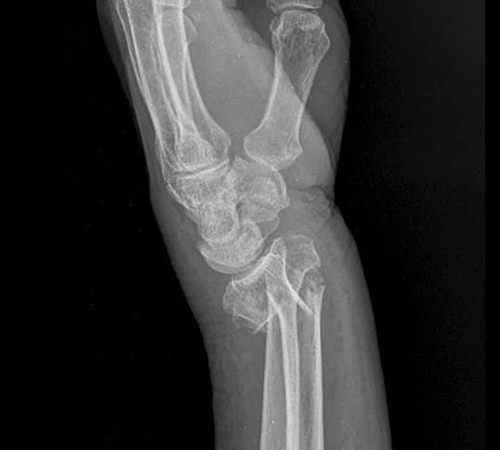

원위요골골절

• 원위요골골절

• 원위요골골절 진단

단순한 X-ray 검사로도 쉽게 진단됩니다.

관절이 심하게 침범된 경우, 컴퓨터 단층 촬영(CT)이 필요하기도 합니다.